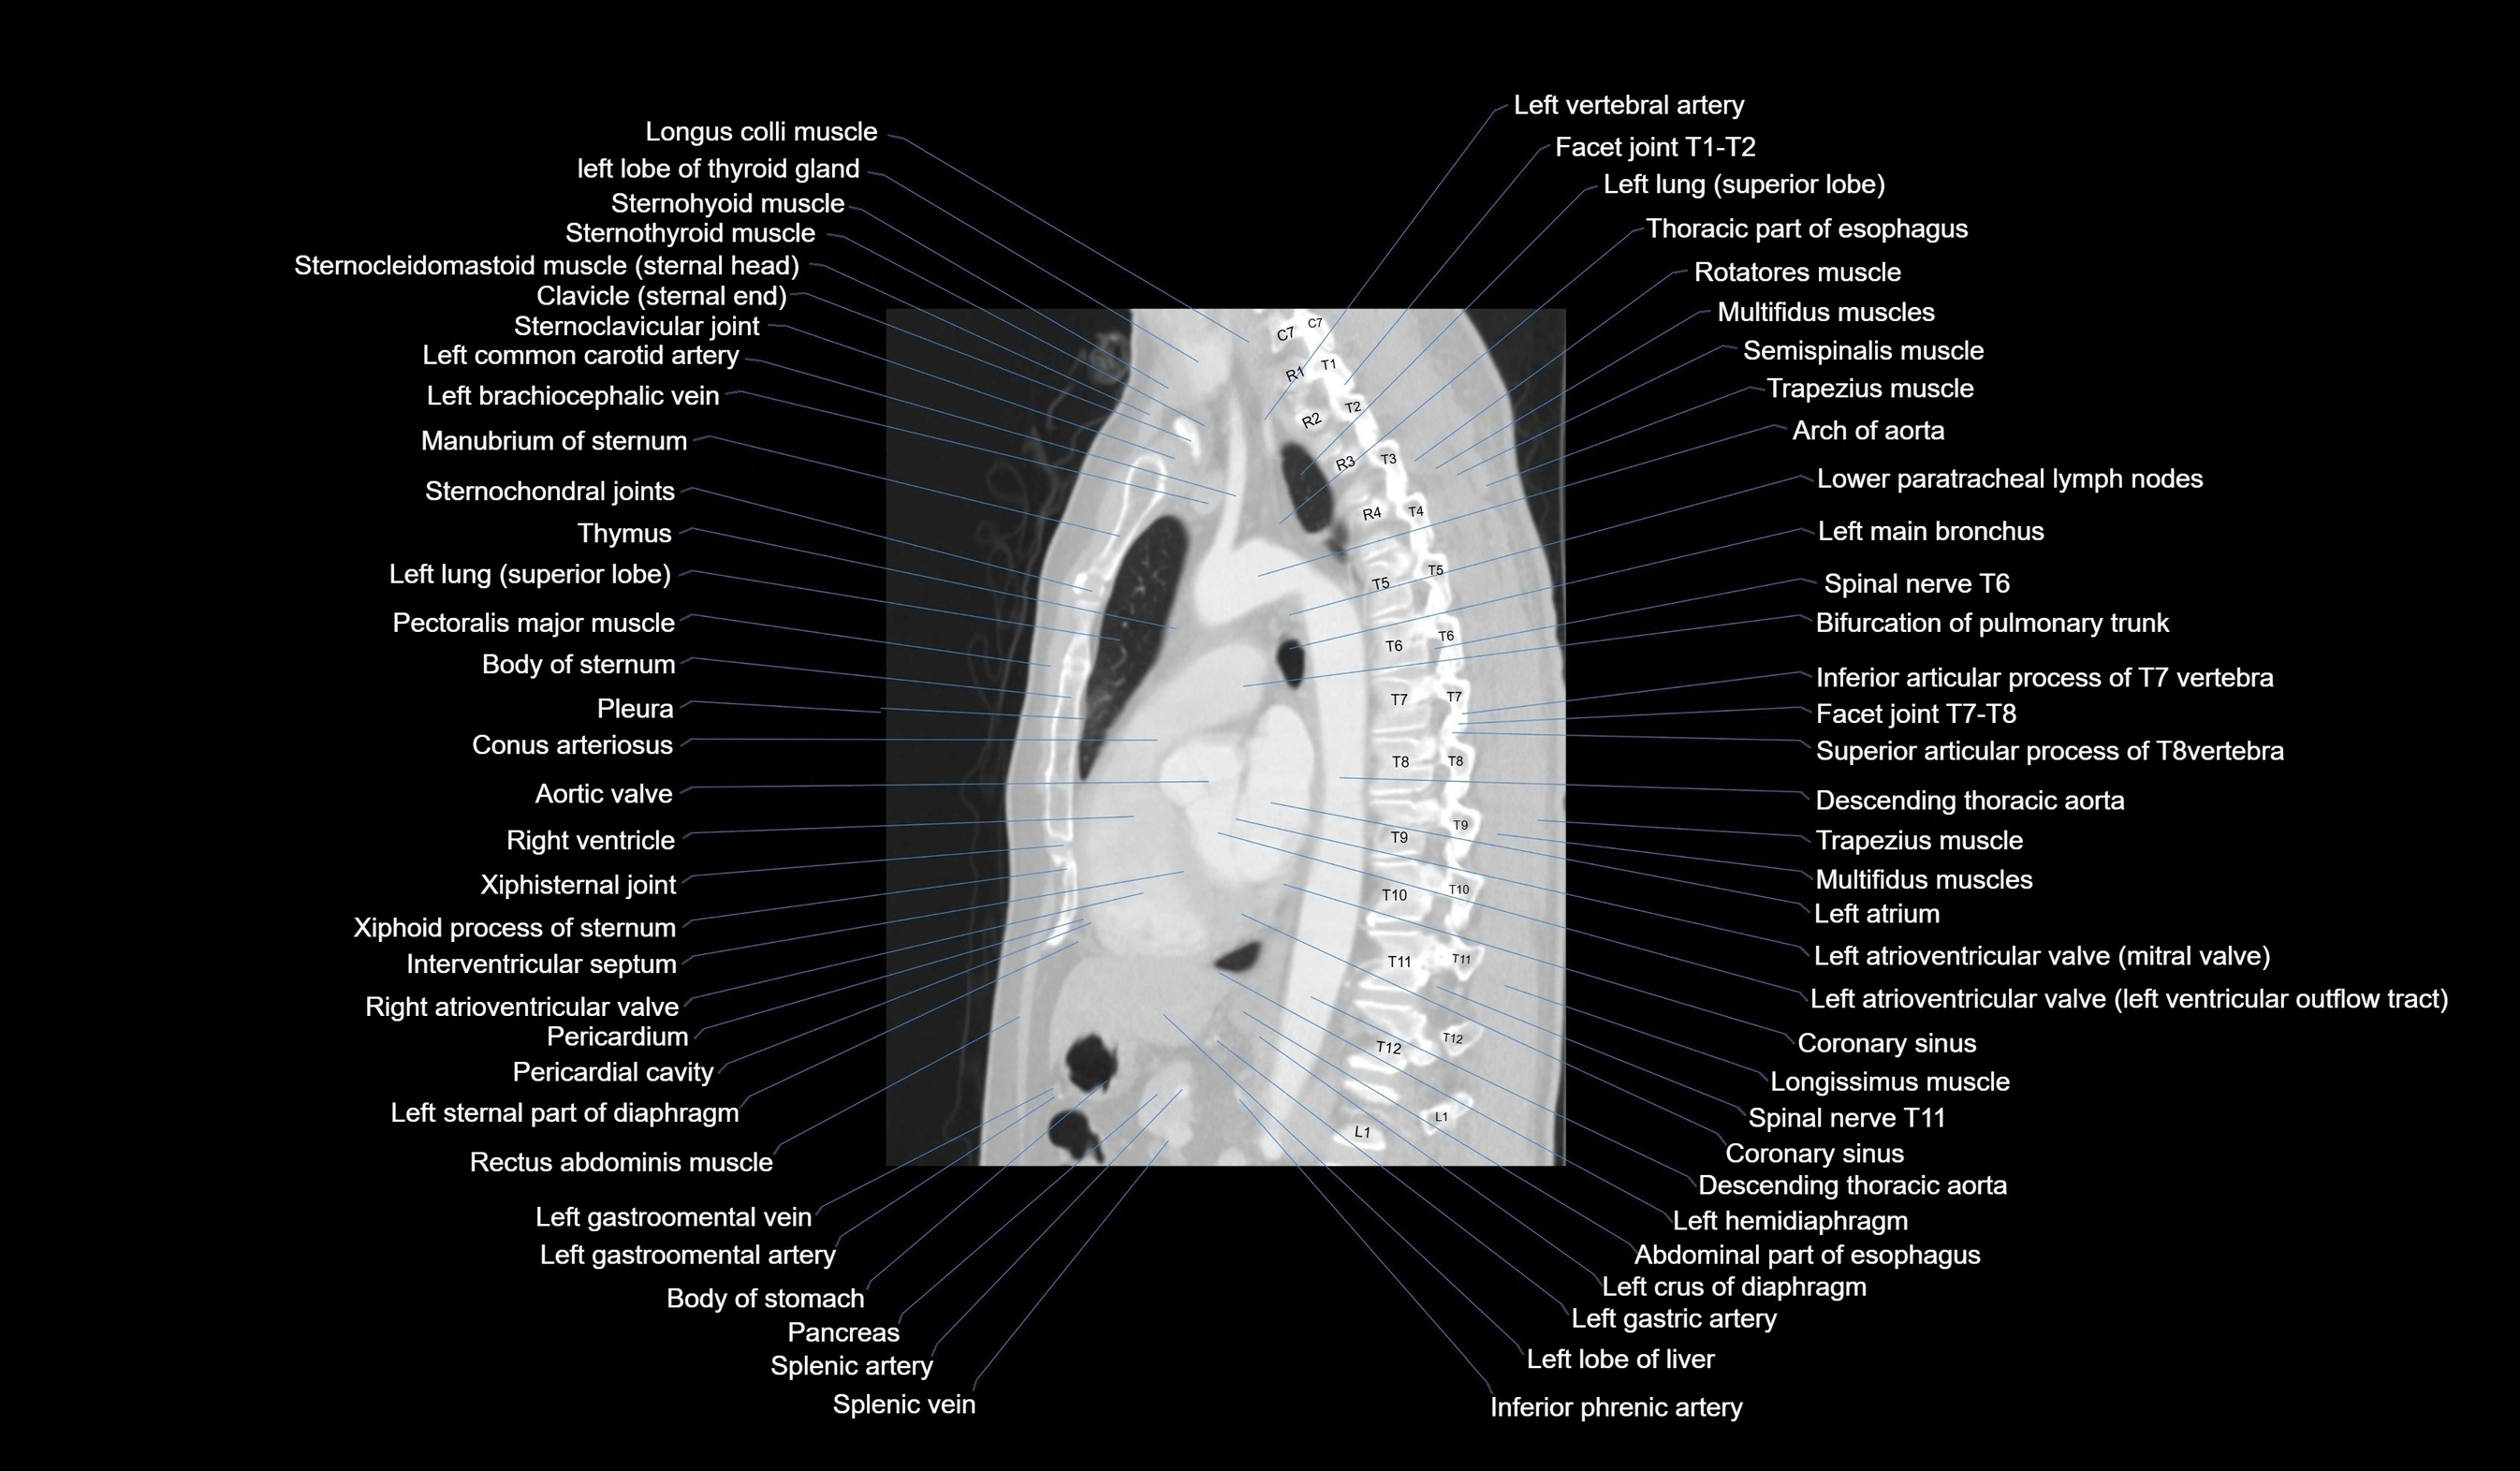

CT images